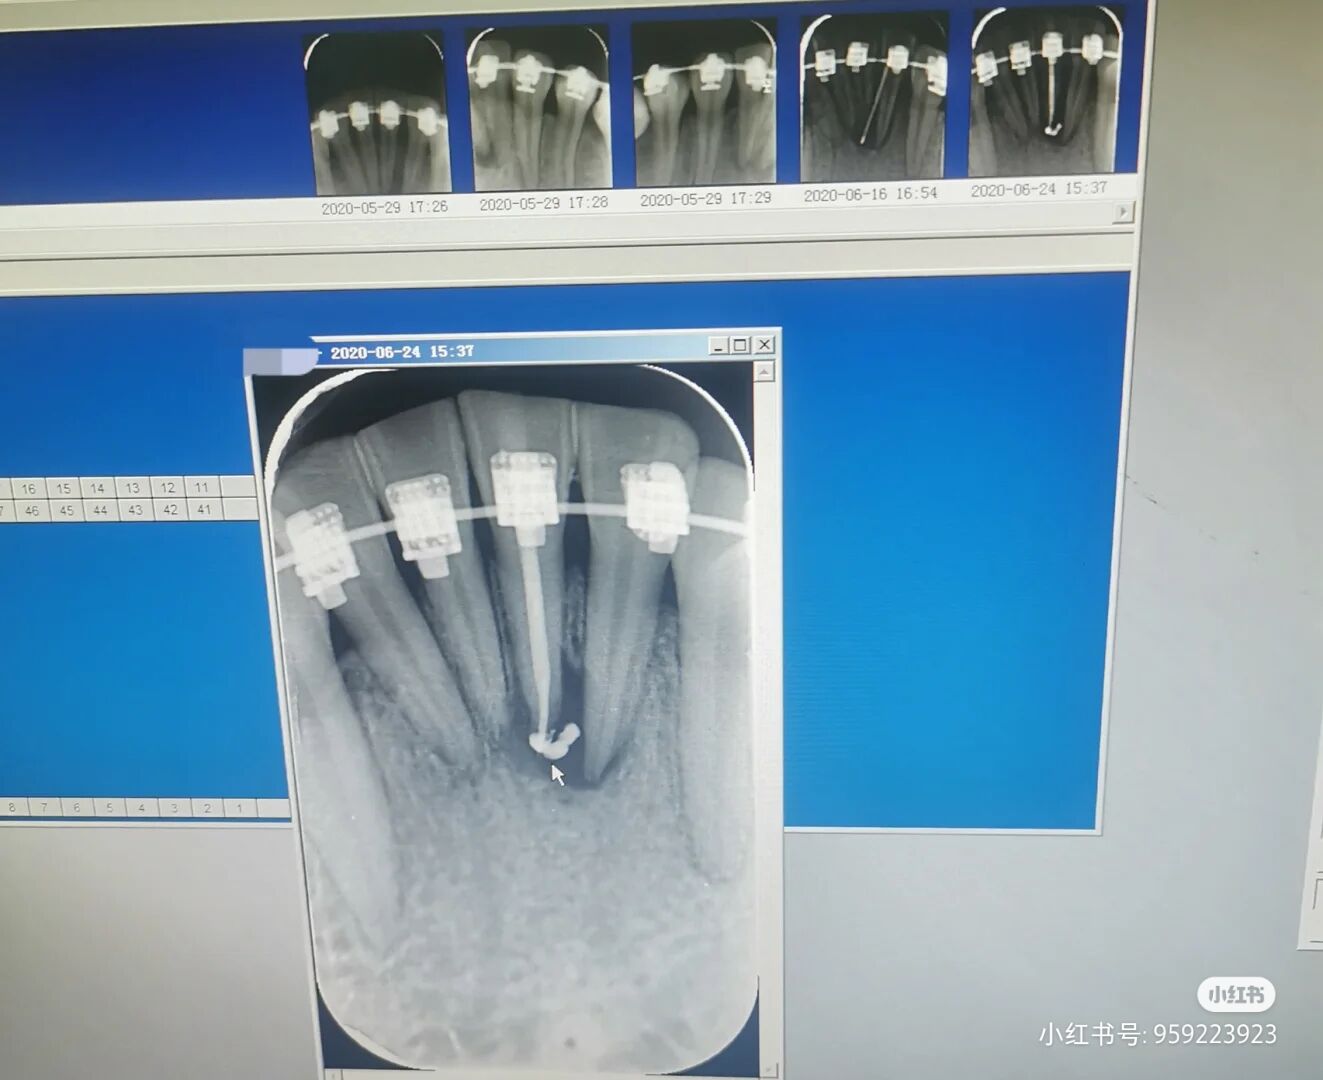

在正畸期间我下牙有脓包肿起,牙龈也肿起,甚至还会疼痛,甚至周边朋友发现我的下牙几乎快飘出来了,我多次询问我的正畸医生,被告知一切正常,是我多虑了。到了去年年底,(脓肿一直存在)我向医生提出问题,说我正畸这么久我的牙齿是一点变化都没有呀,这时医生就告诉我,我这是骨性,说我正畸没用,叫我进行拔牙,但是正畸之前告知我拔牙我的嘴巴没内缩。医生说相信他,让我年后来拔牙,疫情一拖就四五月,我等到开业马上过去拔牙,这时医生说你不是来拔智齿吗?我惊呆了,我说不是你让我来年后拔牙解决我凸度问题吗?医生让我看我自己牙片,再次告诉我我的牙齿骨性也严重,拔牙打骨钉都没什么变化,让我去做手术。叫我下个月拆了。

期间疼痛一直伴随,但一直被告知正常,实在受不了牙齿的丑陋跟疼痛的伴随,奔赴三甲医院检查才知道得了瘘管。

就是好好的下牙变成死牙,牙髓坏死,做了跟管治疗,医生告知让我恢复几个月看下能不能好转。

大概三个月我发现疼痛依然存在,夜里睡不着只能含着棉球咬在疼痛位置,再次挂号三甲医院,这次我才发现我的牙齿不只是瘘管的问题。

医生说我的牙齿基本可以宣布死亡了呀,我的下牙成水平状态,牙根脱离骨头,甚至种植医生告知,我连种植的机会都没有,看看正畸医生能否拯救一下。医生建议我去上海九院,这里实在不敢接手。